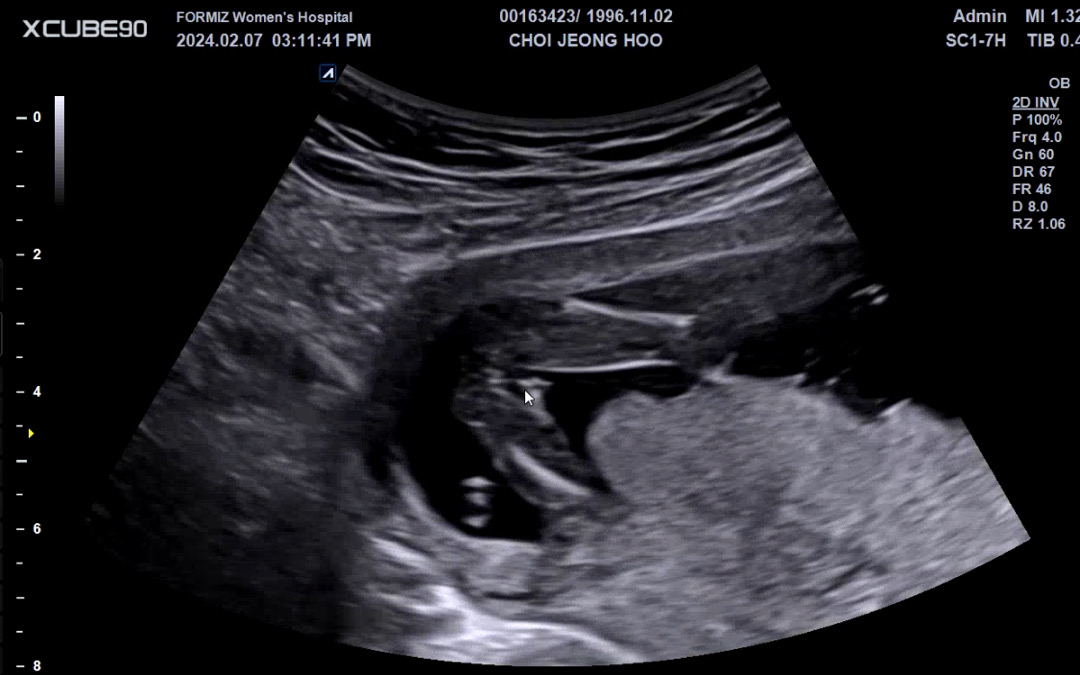

딸일까요? 아들일까요??

고수님들 봐주세요~!

미사일모양이 좀 애매해보이는데 탯줄인거 같기도 하구요 고수는 아니지만 딸에 한표 던져봅니당🙂